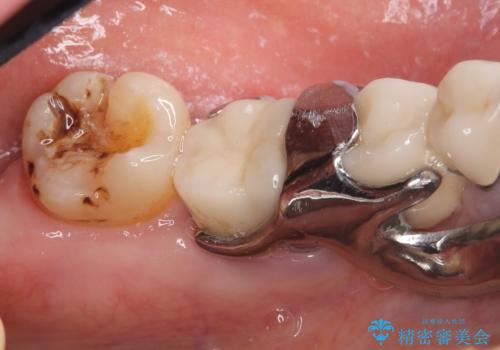

- 主訴:左下一番奥の銀の詰め物が外れてしまった。やり替えを機に綺麗なものを入れたい。

保険のメタルインレー脱離によるやり替え希望だったため、審美性・清掃性の良いセラミックインレーでのやり替えとなりました。

メタルインレー脱離後の窩洞をセラミックインレー窩洞に再形成し直し印象しています。遠心・舌側面のカリエスの除去、残存歯質の破折リスクを考えアンレー形態となりました。